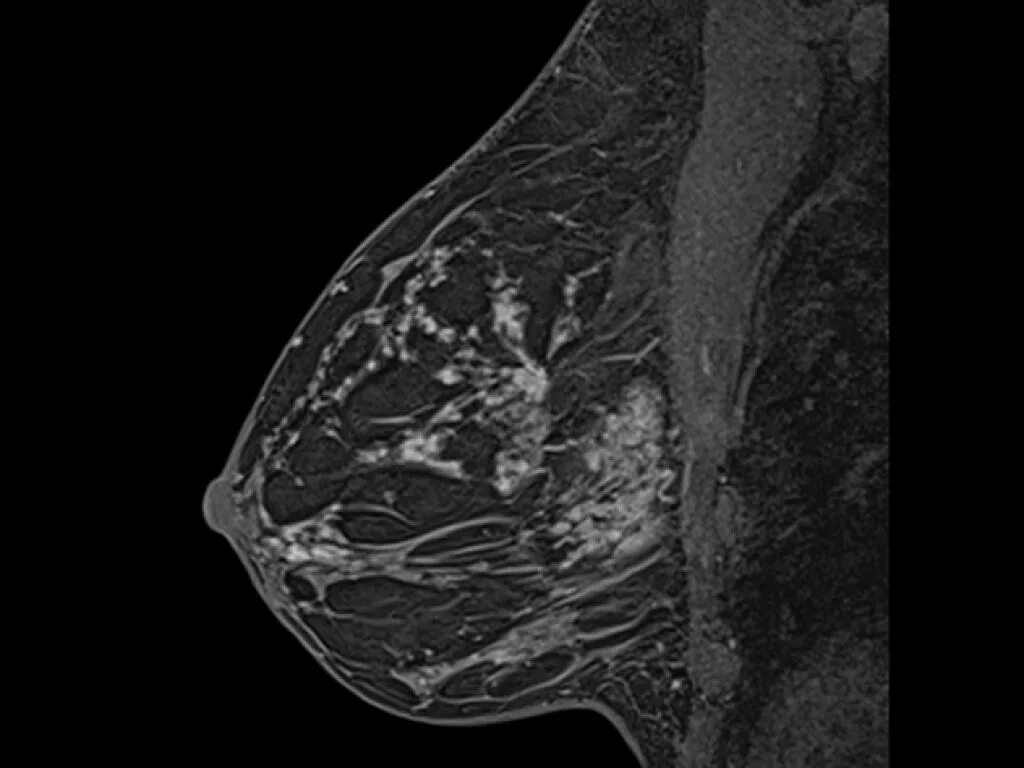

Мрт молочных желез